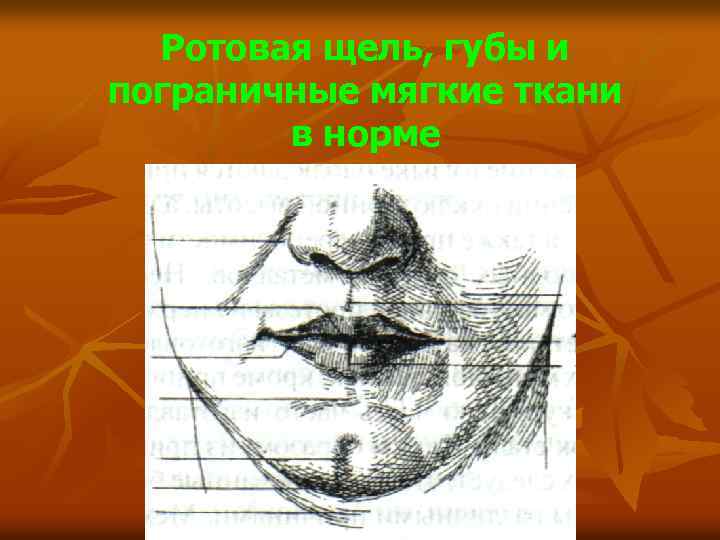

Ротовая щель, губы и пограничные мягкие ткани в норме